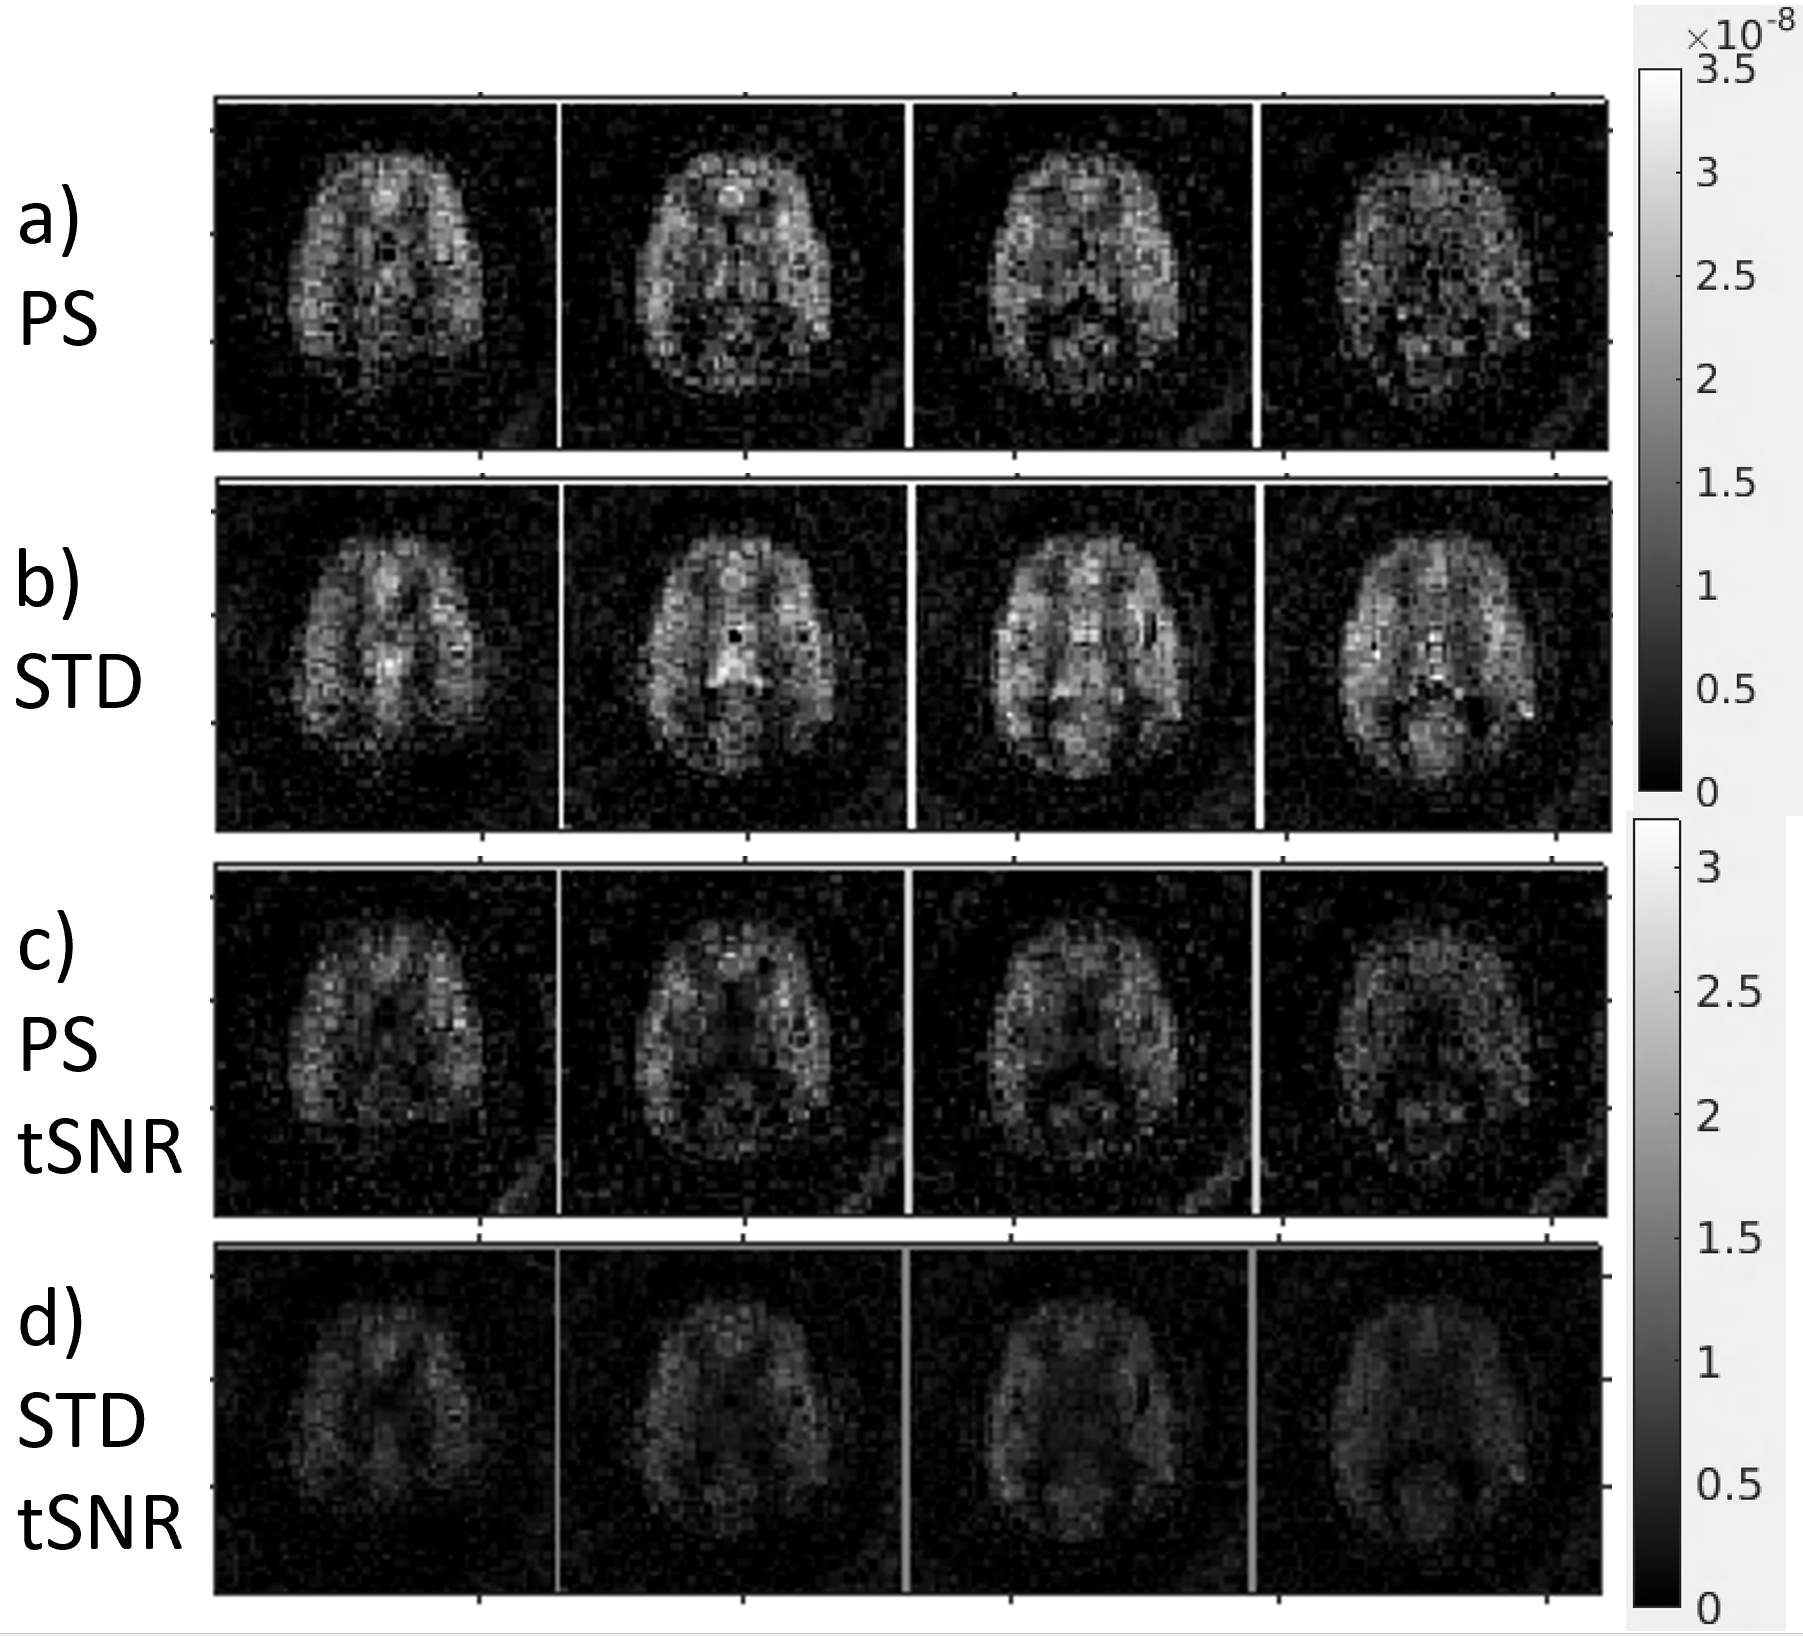

Figure 2 shows that the PS has a lower MSE, a higher SSIM, and a higher AUC compared to STD using the simulation. Figure 3 shows that PS has a higher sharpness in the coronal direction due to higher signal in the higher spatial frequencies. Figure 4 shows that PS has a higher tSNR than STD. Figure 5 shows the activation maps for PS detects activation of the motor cortex due to finger tapping.

Figure 4: Representative axial slices; a) shows the temporal axial mean perfusion for PS and b) shows the axial mean perfusion for STD. The scale for a) and b) in arbitrary units is shown to the right of them. c) shows the temporal SNR for PS and d) shows the temporal SNR for STD. The scale for c) and d) is shown to the right of them. The temporal SNR measurements were found by pixel-wise averaging of the perfusion signal across time divided by the standard deviation of the perfusion signal across time.